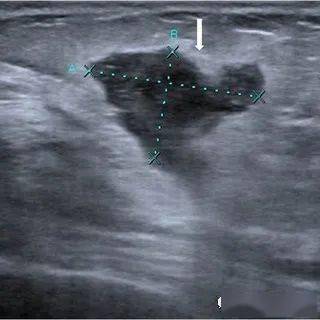

乳腺病例, - 超声医学讨论版 - 爱爱医医学论坛

乳腺炎常见,但乳头炎性病变你遇到过没有?_超声